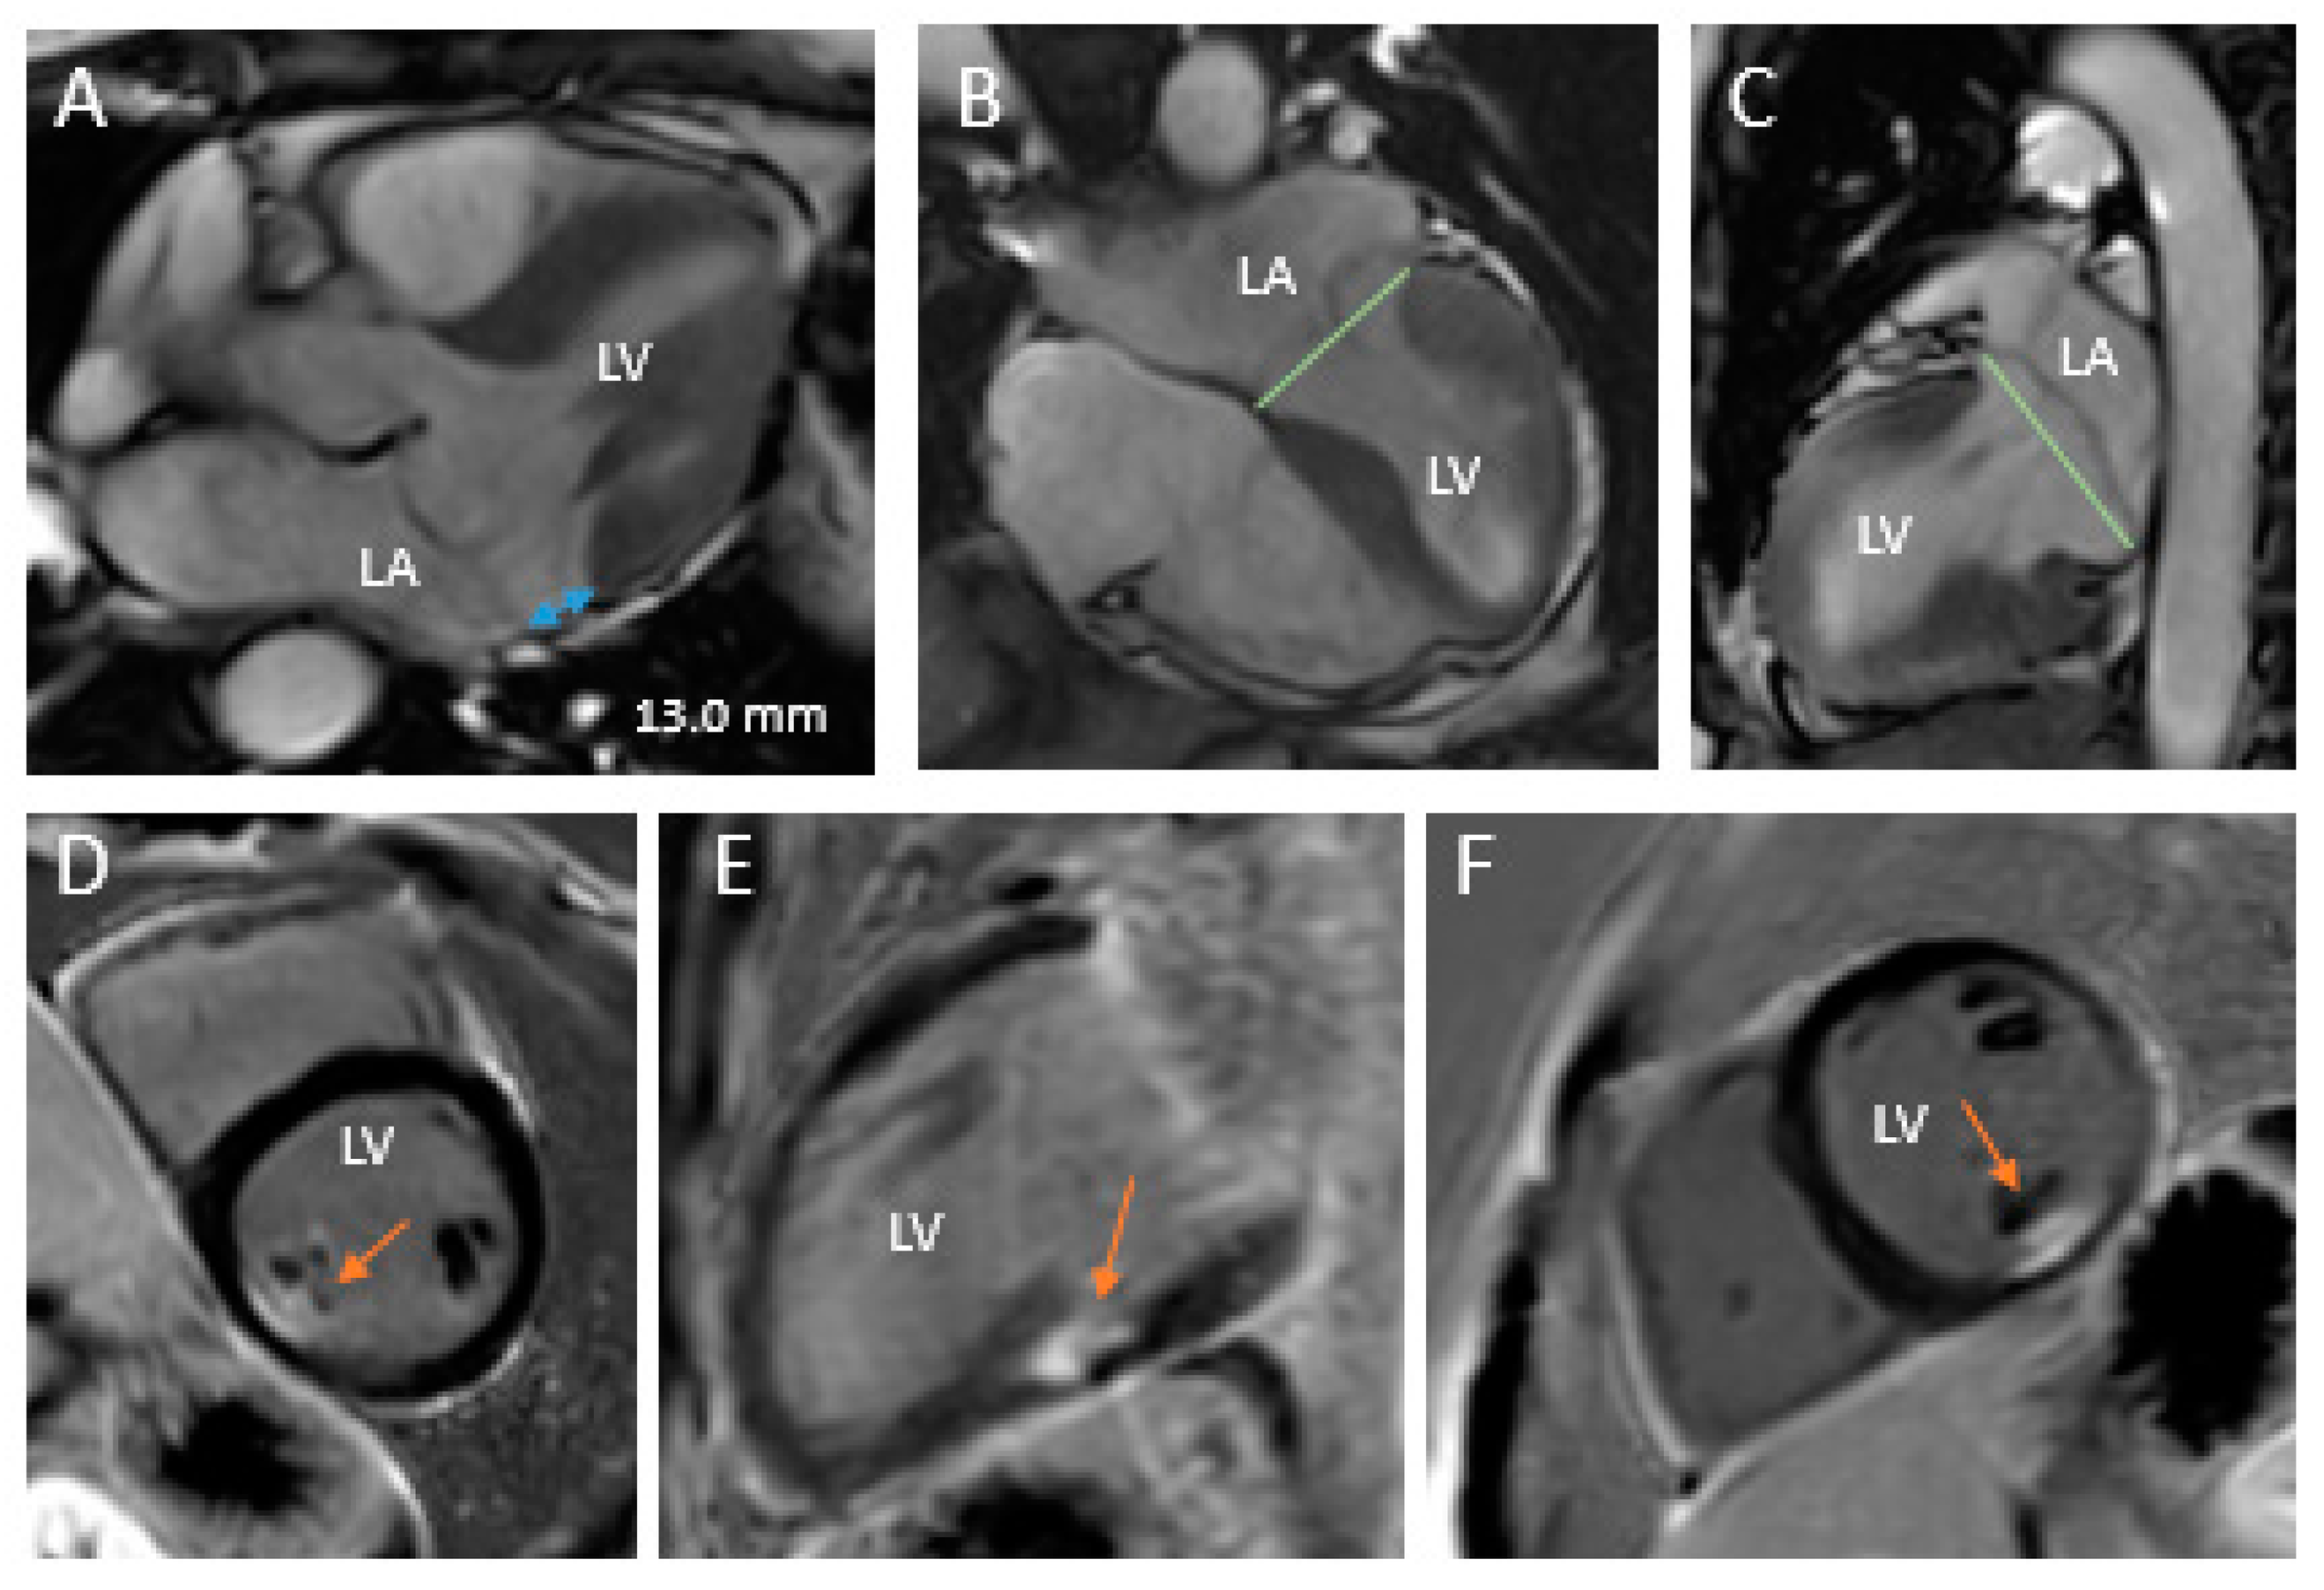

- Chandra, S.; Salgo, I.S.; Sugeng, L.; Weinert, L.; Tsang, W.; Takeuchi, M.; Spencer, K.T.; O’Connor, A.; Cardinale, M.; Settlemier, S.; et al. Characterization of degenerative mitral valve disease using morphologic analysis of real-time three-dimensional echocardiographic images: Objective insight into complexity and planning of mitral valve repair. Circ. Cardiovasc. Imaging 2011, 4, 24–32. [Google Scholar] [CrossRef]

- Clavel, M.A.; Mantovani, F.; Malouf, J.; Michelena, H.I.; Vatury, O.; Jain, M.S.; Mankad, S.V.; Suri, R.M.; Enriquez-Sarano, M. Dynamic phenotypes of degenerative myxomatous mitral valve disease: Quantitative 3-dimensional echocardiographic study. Circ. Cardiovasc. Imaging 2015, 8, e002989. [Google Scholar] [CrossRef]

- Viani, G.M.; Leo, L.A.; Borruso, M.G.; Klersy, C.; Paiocchi, V.L.; Schlossbauer, S.A.; Caretta, A.; Demertzis, S.; Faletra, F.F. Mitral annulus morphometry in degenerative mitral regurgitation phenotypes. Echocardiography 2020, 37, 612–619. [Google Scholar] [CrossRef]

| Leaflets | Single segment (usually posterior) prolapse (flail) due to chordal rupture Thickened leaflet tissue (when present) is limited to the level of the prolapsing segment Thin/normal leaflet tissue in non-prolapsing segments | Diffuse excessive valve tissue with multiple segments, bi-leaflet prolapse Thickened leaflets |

| Annulus | Normal of moderate annular dilatation No calcifications | Severe annular dilatation Calcifications could be present Mitral annular disjunction Systolic outward motion during systole (curling) |

| Chordae | Chordal rupture of the involved segment | Elongated or ruptured Thickened and/or calcified |